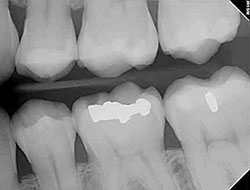

Digital X-rays provide several advanced imaging options designed to save time, provide clearer dental photos, and expose patients to less radiation than traditional X-ray technology.